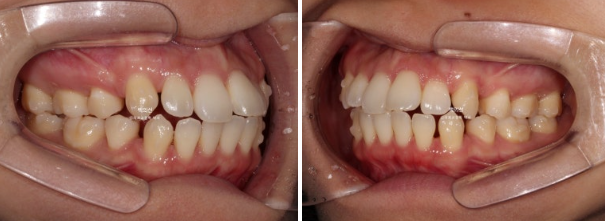

인비절라인을 원하셔서 인비절라인 발치교정을 권유드렸습니다.

작은어금니 4개를 발치하기로 했습니다.

첫번째 세트의 장치는 총 80개가 나왔습니다.

일주일에 한 개씩 장치를 교체하며 진행했습니다.

24.01

치료시작 1년째 모습입니다.

발치공간은 절반쯤 없어졌고

장치가 뜨거나 안 맞는 부분이 없이 치료가 잘 되어가고 있습니다.